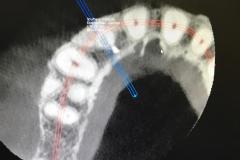

Implants placed using a digitally planned stackable surgical guide following alveolectomy, ensuring ideal positioning and a stable foundation for full-arch restoration.